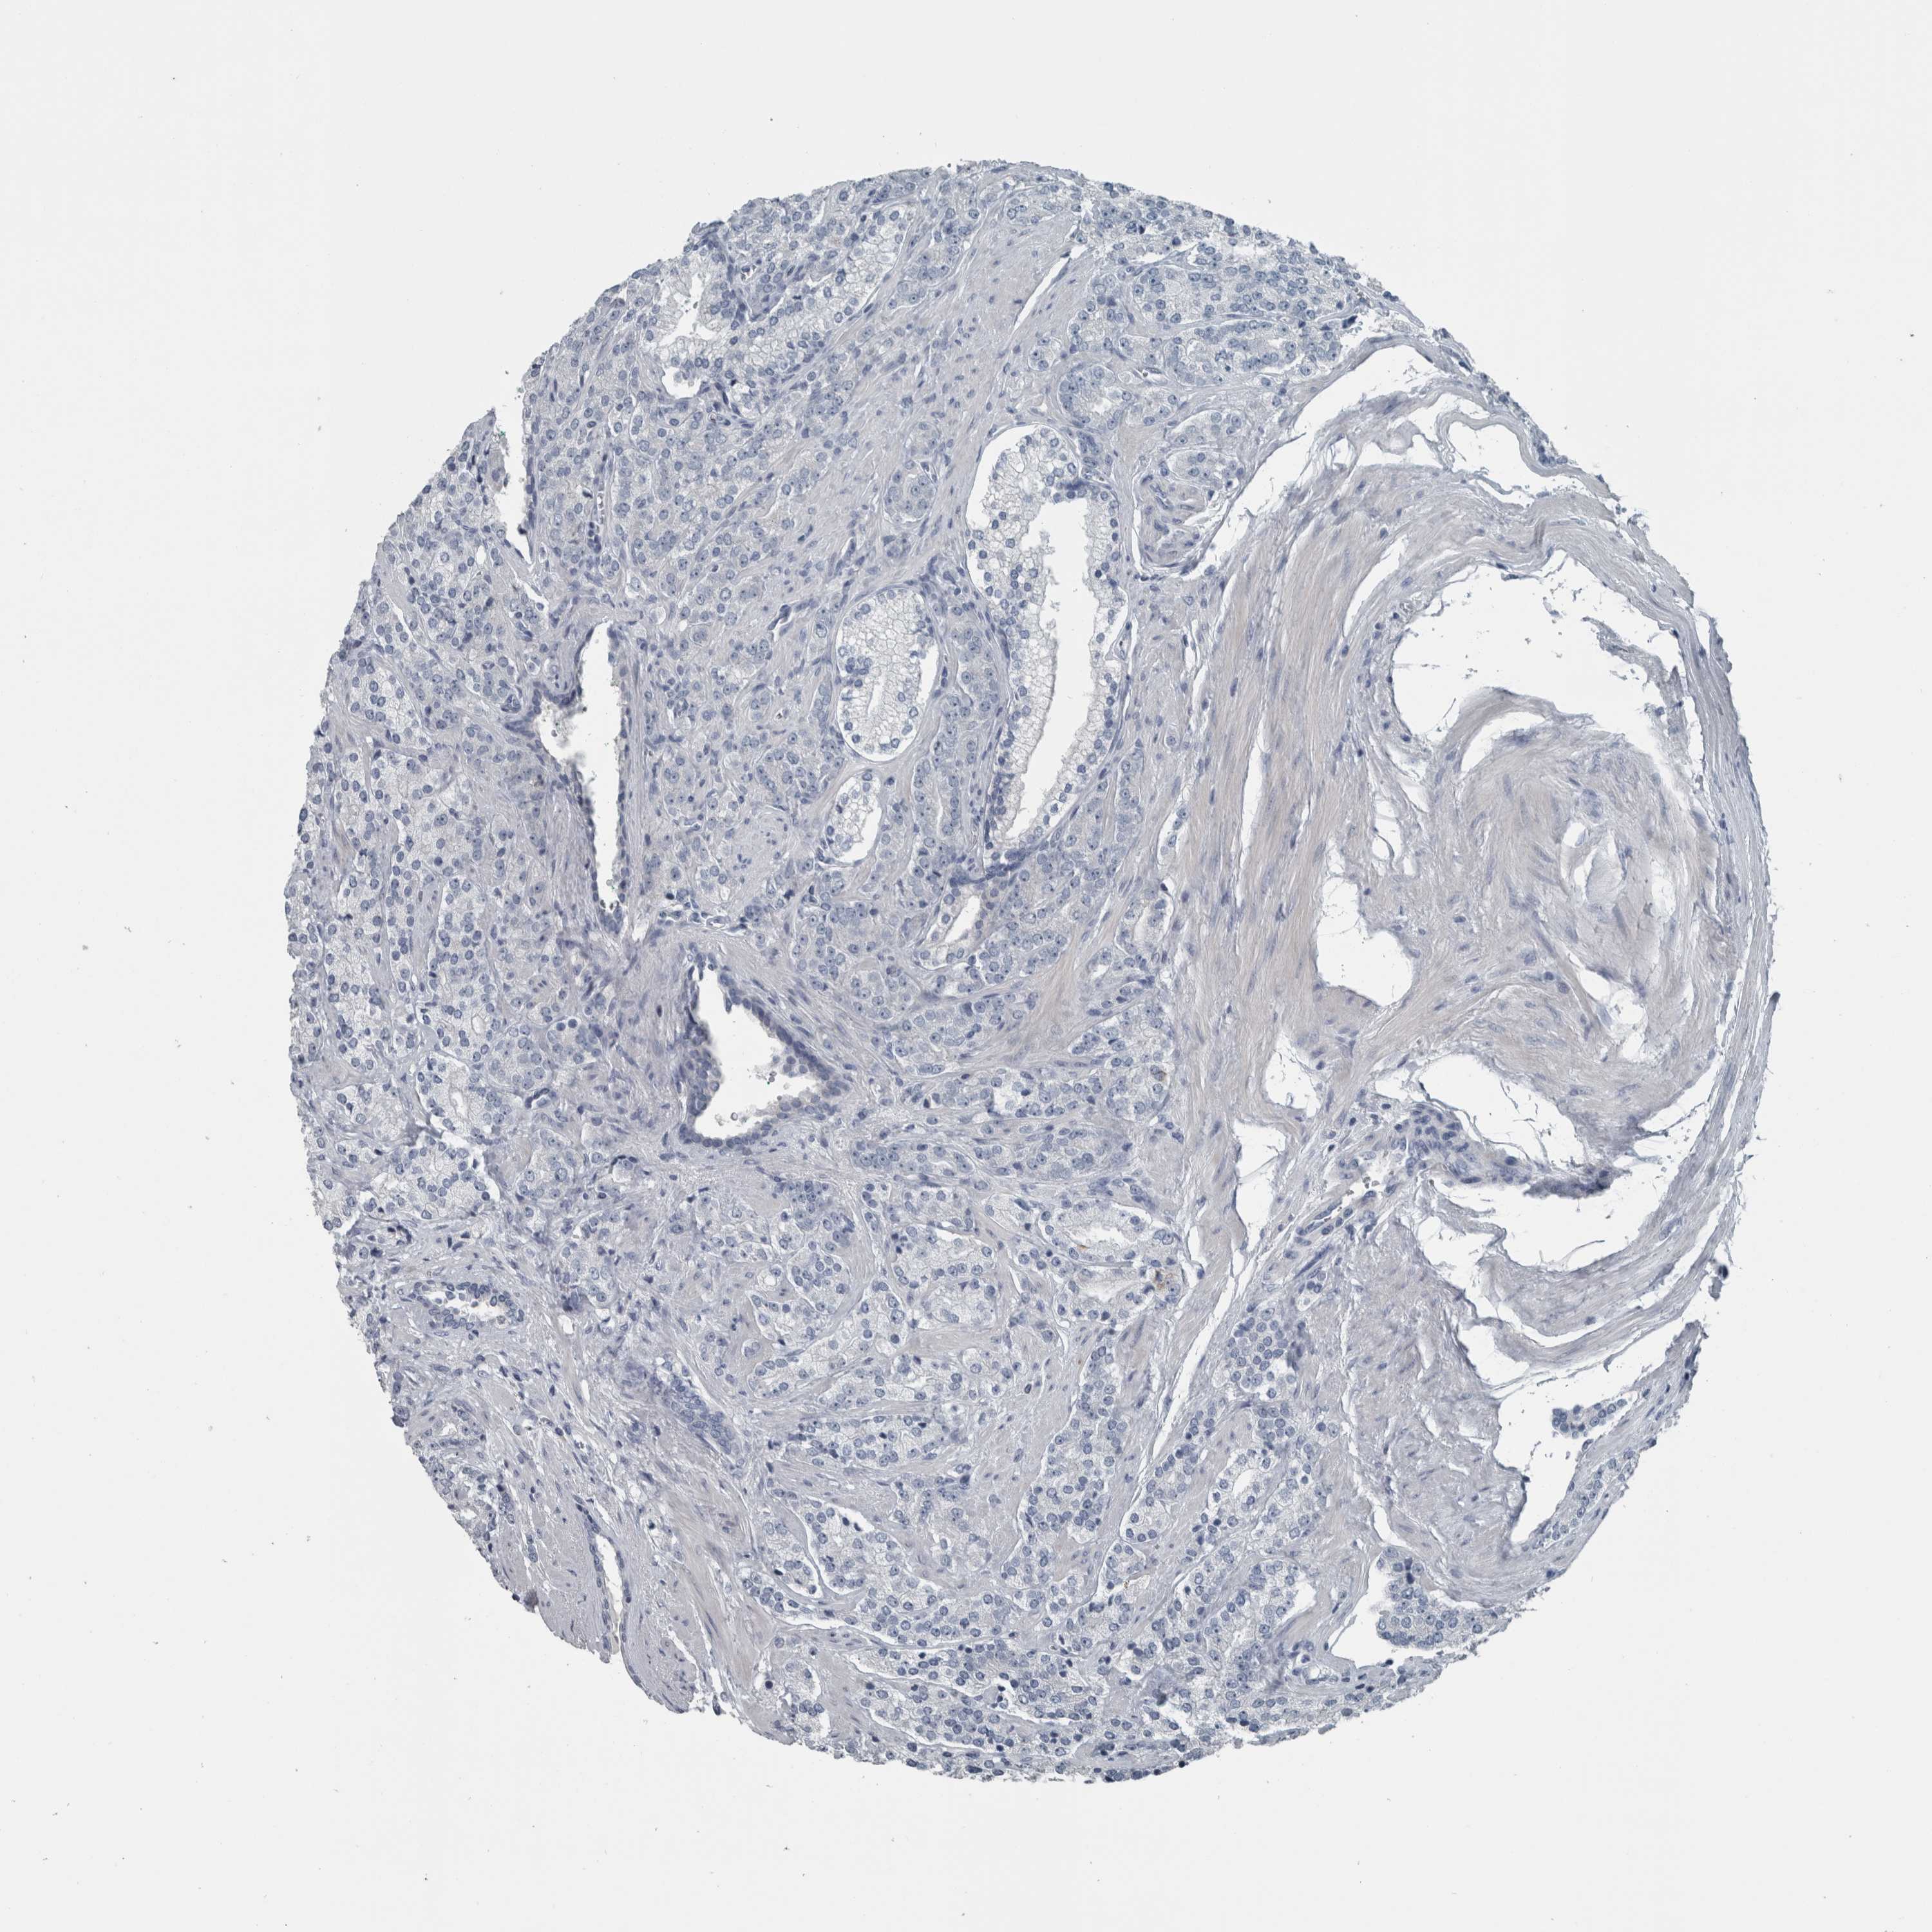

PROSTATE CANCER - Protein expressioni

A mouse-over function shows sample information and annotation data. Click on an image to view it in a full screen mode. Samples can be filtered based on level of antibody staining by selecting one or several of the following categories: high, medium, low and not detected. The assay and annotation is described here.

Note that samples used for immunohistochemistry by the Human Protein Atlas do not correspond to samples in the TCGA dataset.

Antibody stainingi

Antibody staining in the annotated cell types in the current human tissue is reported as not detected, low, medium, or high, based on conventional immunohistochemistry profiling in selected tissues. This score is based on the combination of the staining intensity and fraction of stained cells.

Each image is clickable and will lead to virtual microscopy that enables deeper exploration of all samples and also displays staining intensity scores, fraction scores and subcellular localization as well as patient and tissue information for each sample.

Antibody HPA024309

Antibody HPA024684

Antibody HPA027236

Antibody CAB000032

Staining

High

Medium

Low

Not detected

Intensity

Strong

Moderate

Weak

Negative

Quantity

>75%

75%-25%

<25%

None

Location

Nuclear

Cytoplasmic/membranous

Cytoplasmic/membranous,nuclear

Adenocarcinoma, High grade

Adenocarcinoma, Low grade

Adenocarcinoma, Medium grade